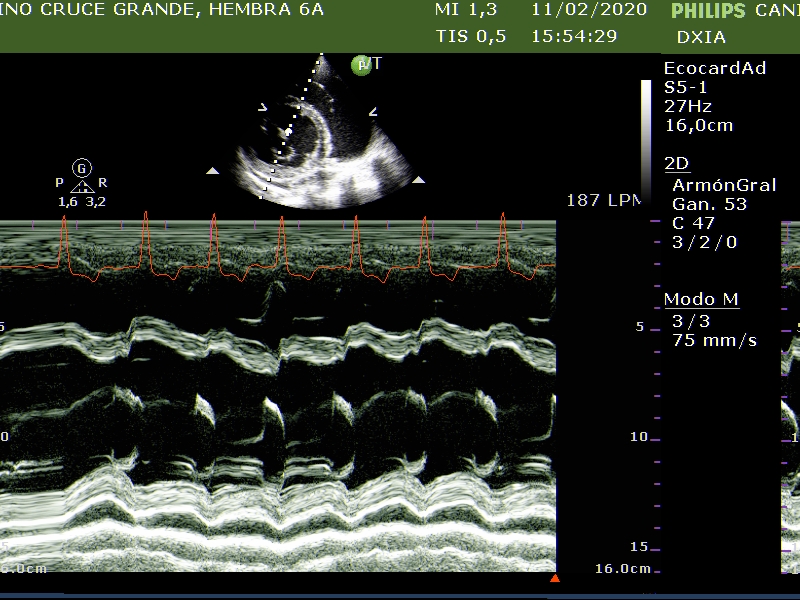

Comentario respecto al estudio ecocardiográfico:

- Derrame pericárdico sin taponamiento cardiaco.

- Marcada dilatación de cámaras cardiacas.

- Engrosamiento nodular de la VM compatible con posible enfermedad degenerativa.

- Flujo regurgitante mitrálico y tricuspídeo.

- FA, SSPVE, IE compatible con CMD.

- ECG: Fibrilación atrial de base con presencia de CPVs aislados.

La paciente presenta CMD con cambios nodulares en las valvas de la VM ¿CMD Y/O DVM?